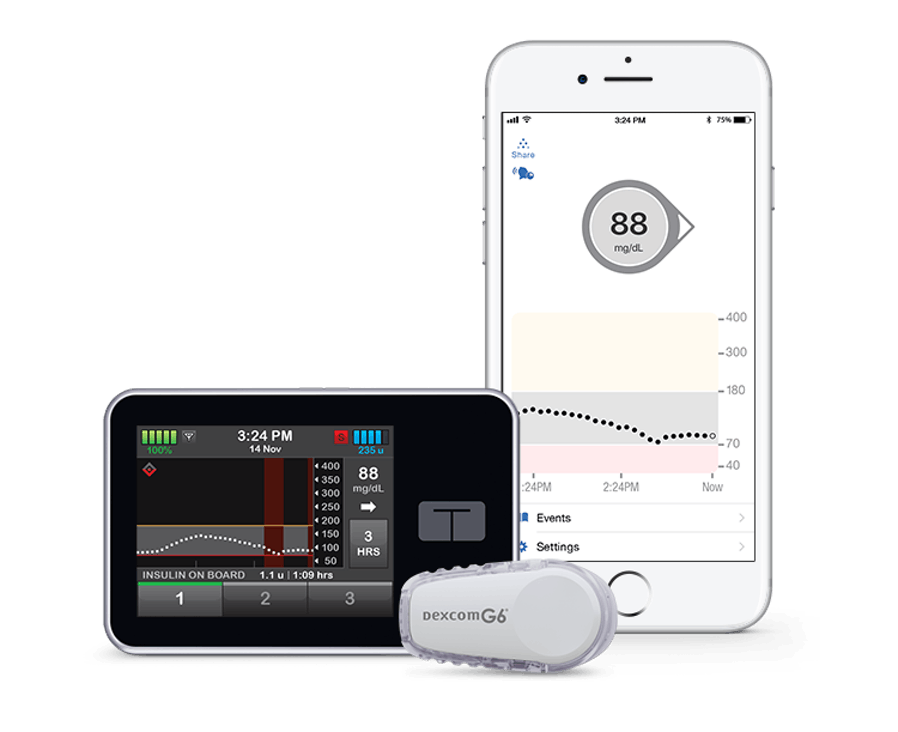

La bomba t: slim X2 se puede usar como una bomba de insulina independiente, o puede integrarla con el sistema de Monitoreo Continuo de Glucosa (CGM) Dexcom G6. Cuando se usa con Dexcom G6, usted puede elegir una de las dos tecnologías predictivas (Control-IQ™ o Basal-IQ®), que ayudan a administrar insulina, lo que simplifica el manejo de la diabetes.

La integración de Dexcom G6 CGM con la Bomba de Insulina t:slim X2 proporciona una precisión excepcional para optimizar la administración de insulina. Dexcom G6 es el primer Sistema Integrado de Monitoreo Continuo de Glucosa en tiempo real (iCGM) que requiere Cero Pinchazos en los dedos para calibraciones o dosificaciones a la hora de comer.

La aplicación móvil t: connect® sirve como una pantalla secundaria discreta para su bomba de insulina t: slim X2, para que pueda mantenerse informado sobre el manejo de su diabetes desde la comodidad de su teléfono. Vea los datos de su bomba, incluidos los eventos de insulina basal y de bolo, la insulina a bordo, los carbohidratos, la configuración y el estado de la bomba y el sensor.

La integración de Dexcom G6 CGM con la Bomba t:slim X2 brinda una precisión excepcional para optimizar la administración de insulina. Dexcom G6 es el primer sistema integrado de Monitoreo Ccontinuo de Glucosa (iCGM) en tiempo real que no requiere PINCHAZOS en los dedos para la calibración o la dosificación a la hora de comer.†